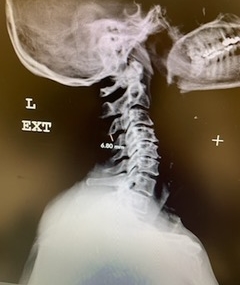

(2a) Lateral Flexion cervical x-rays demonstrating 8mm of splaying of the C34 interspinous distance

The fluid was possibly consistent with CSF versus chronic hematoma. The patient was also noted to have a high signal within the interspinous space of C3-C4. This high signal was consistent with a ruptured C3-4 interspinous ligament. Cervical flexion-extension x-rays demonstrated 6 mm of widening of the C3-4 interspinous space on flexion x-ray consistent with cervical instability (Fig. 2a and 2b).